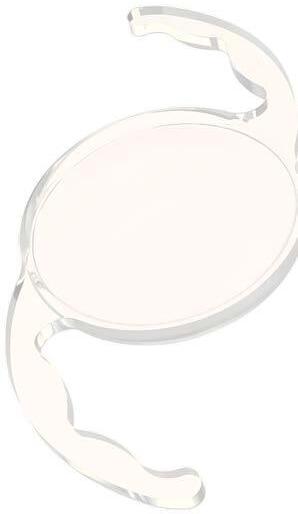

Clareon® PanOptix® de Alcon: Esta innovadora lente trifocal representa la evolución del reconocido modelo PanOptix® , ahora combinada con el nuevo material Clareon®. El Clareon® es un acrílico hidrofóbico de última generación, con una pureza y claridad superior, que elimina virtualmente la aparición de “glistenings” o microvacuolas. Esto se traduce en una mayor estabilidad refractiva y una calidad visual sostenida a largo plazo. La óptica trifocal permite a los pacientes obtener una visión excelente a distancia, intermedia (ideal para computadoras) y cercana (lectura), con una mínima dependencia de anteojos. En el marco del congreso, se presentaron estudios multicéntricos que mostraron altos niveles de satisfacción y nitidez visual incluso en condiciones de baja iluminación, posicionando a esta lente como una de las más completas para pacientes activos con altas expectativas visuales.

RayOne Galaxy de Rayner : Una de las grandes novedades del ASCRS 2025, fue presentada como la primera lente intraocular diseñada con el apoyo de inteligencia artificial. Se trata de una lente no difractiva con óptica espiral progresiva, lo que permite una transición suave y continua entre diferentes distancias focales sin los efectos secundarios típicos de otras lentes multifocales, como halos o deslumbramientos nocturnos.

Su diseño aprovecha algoritmos de inteligencia artificial entrenados en miles de casos reales para optimizar la distribución de luz en función del tamaño pupilar y las condiciones de iluminación. Además, la lente se inyecta mediante el sistema RayOne preloaded , que asegura una implantación precisa y segura, reduciendo el tiempo quirúrgico.

Esta LIO se perfila como una opción atractiva para pacientes que buscan independencia de gafas con excelente calidad visual en todas las distancias, incluso en pacientes con córneas ligeramente irregulares.

Apthera IC-8 de Bausch + Lomb : Esta lente de apertura pequeña no tórica está diseñada para pacientes con astigmatismo corneal de hasta 1.5 D, ofreciendo una solución eficaz para la presbicia y mejorando la calidad visual en condiciones de baja iluminación.